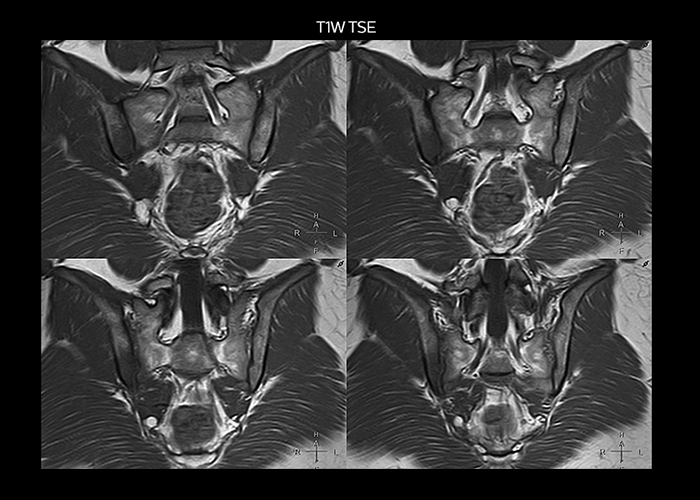

“On average, we scan about 80 patients per day, but on some days we scan well over 100 patients. The scanner is in use 7 days per week, operated 20 hours per day on week days and 8 hours per day in the weekend,” Mr. Tuna says. “To avoid coil changes we plan examinations of similar anatomies back to back, such as head and spine. Multiva helps us here a lot because coils don’t need to be changed frequently. Moreover, thanks to parallel imaging technology and 16-channel HeadSpineTorso and 8-channel MSK coils we are able to achieve excellent image quality. In this way Multiva helped us to increase both image quality and productivity.” “Neurological cases, such as brain and spine imaging, represent the largest share in our MR scanning, followed by musculoskeletal cases. In general, we use simple and basic imaging protocols. But occasionally, we use advanced techniques for problematic cases if necessary.